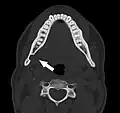

![]() | |

| Dental panoramic radiograph showing Stafne defect in the right mandible, below the inferior alveolar nerve canal (arrowed, appears on lower left of image). This x-ray was taken for an unrelated assessment of wisdom teeth, and the Stafne defect was a chance finding. | |